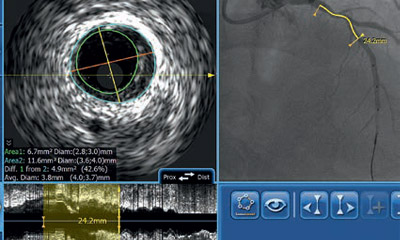

IVUS- und Physiologie Workshop

WORKSHOP

IVUS

Mehr Informationen

Workshops Clock Icon image

Dauer: 1 Tag

Termine 2023:

26.04.

08.11.

Workshops Community Icon image

Teilnehmer:

optimal 6 Personen

Trainer Icon

Fachexperte:

Prof. Dr. med. Michael Haude

Locator Icon image

Ort:

Neuss

IVUS Workshop

IVUS: Grundlagen und Einsatz im Alltag eines Herzkatheterlabors

28.04.

03.11.

optimal 8-10 Personen

Fachexperten:

PD Dr. Moritz Seiffert

Dr. med. Fabian J. Brunner

Hamburg